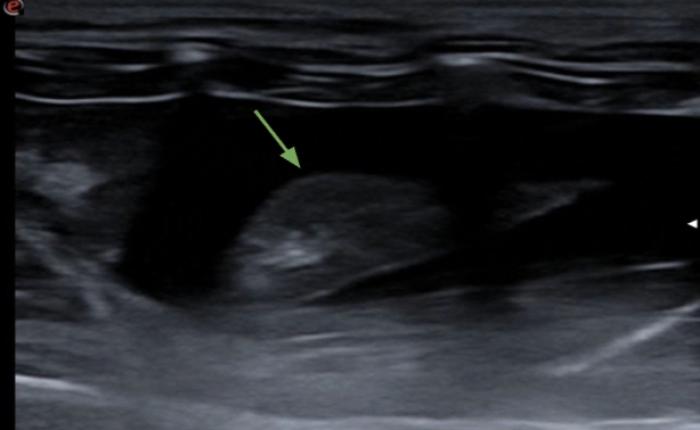

Signo nodular

Consiste en una consolidación de aspecto circular a menudo de anecoicos a hipoecoicos con rara aparición de broncogramas en su interior. Distalmente al signo nodular observamos una línea cóncava hiperecogénica llamada línea C y un refuerzo posterior o signo de brillo en la profundidad del campo. Este hallazgo es común en neoplasias primarias o metastásicas, granulomas fúngicos o abscesos. Es un signo de especial importancia cuando tenemos un paciente con historial oncológico previo o en el protocolo de búsqueda de metástasis. Los nódulos observados veremos cómo se desplazan de izquierda a derecha de la imagen con la respiración del paciente, haciendo patente que se encuentran a nivel pulmonar y no de la pared costal, en cuyo caso no se desplazaran mientras el transductor se encuentre inmóvil (Figura 16A-D).